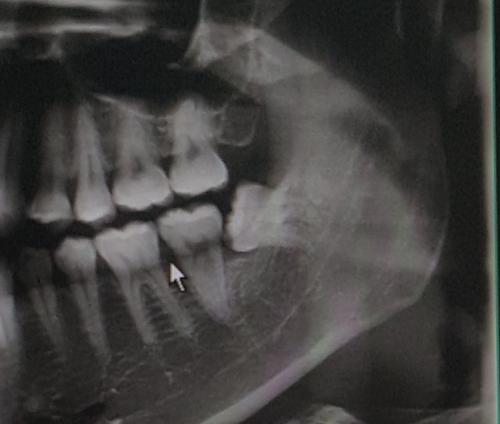

집근처에 사랑니 전문으로 하는데서 2시간 걸렷는데 진짜 힘들엇어요 ㅠㅜ..

치아관리 잘하셨네요 때운곳 없네요 | ||

저도 누워있는 이때문에 나중에 고생할까봐.. 큰맘먹고 뺐습니다. ㅎㅎ | ||